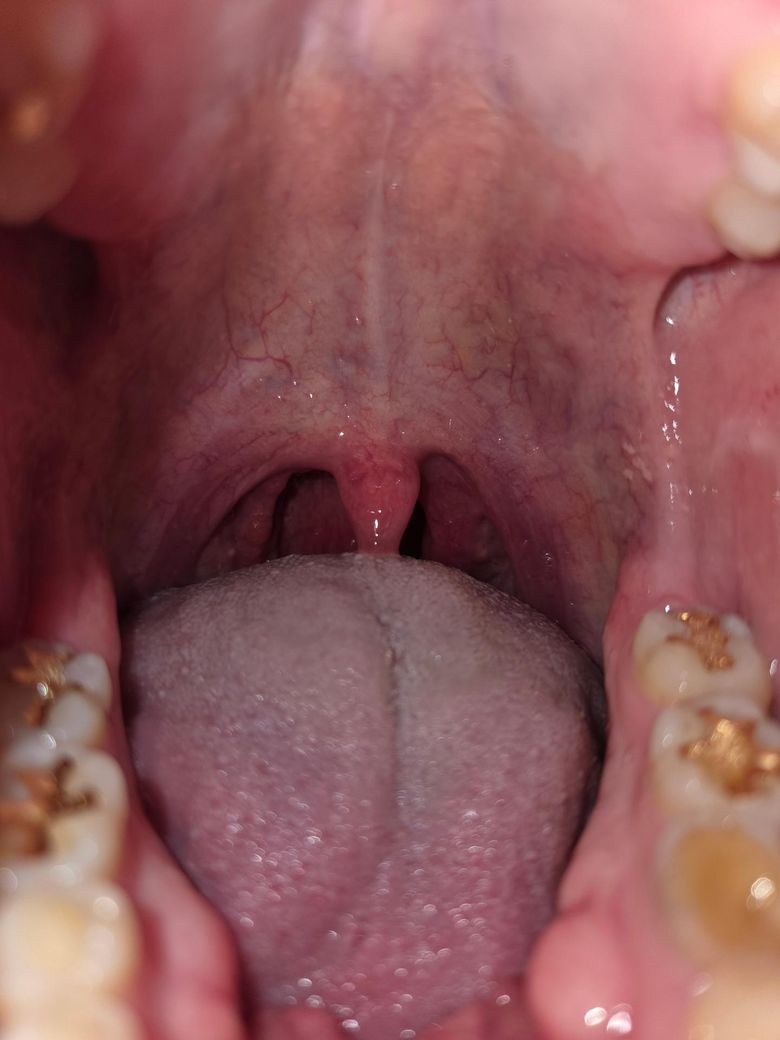

• 1번 째 사진

1.육안으로 보기에는 뚜렷한 감염의 징후는 보이지 않는 것 같습니다.